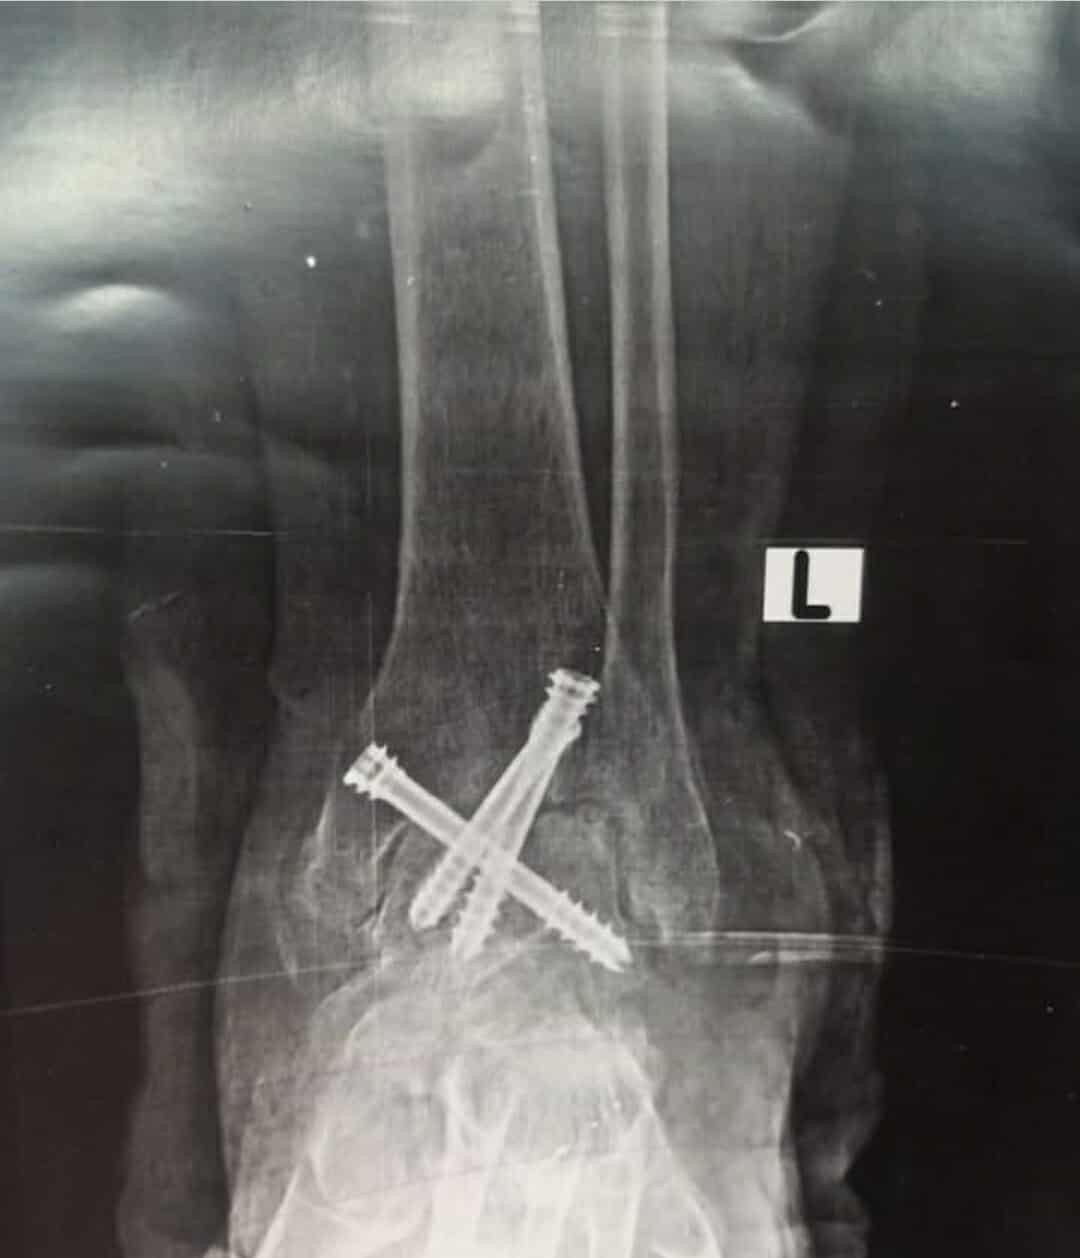

قامت الوحدة بإجراء جراحة لمريض ستيني يعاني من آلام مزمنه وتشوه وتيبس مفصل الكاحل الأيسر وعدم القدرة على المشي بصورة طبيعية حيث تم عمل سمكرة كاملة لمفصل الكاحل لإنهاء معاناة المريض المزمنه عن طريق منظار الكاحل والتدخل الدقيق المحدود والتثبيت بثلاثة مسامير ثنائية الضغط وتمت الجراحة كاملة من خلال جروح بسيطه لا تتعدى واحد سنتيمتر بدون فتح جراحي تقليدي والمريض بصحة جيدة وفي مرحلة التعافي والعلاج

قام بإجراء الجراحة الأستاذ الدكتور أحمد سمير بشندي أستاذ جراحة القدم والكاحل بكلية طب القاهرة ورئيس وحدة القدم والكاحل بمستشفى النيل للتأمين الصحي والدكتور محمد فرحات رئيس قسم العظام والدكتور أحمد عامر مقرر وحدة القدم والكاحل بمستشفى النيل